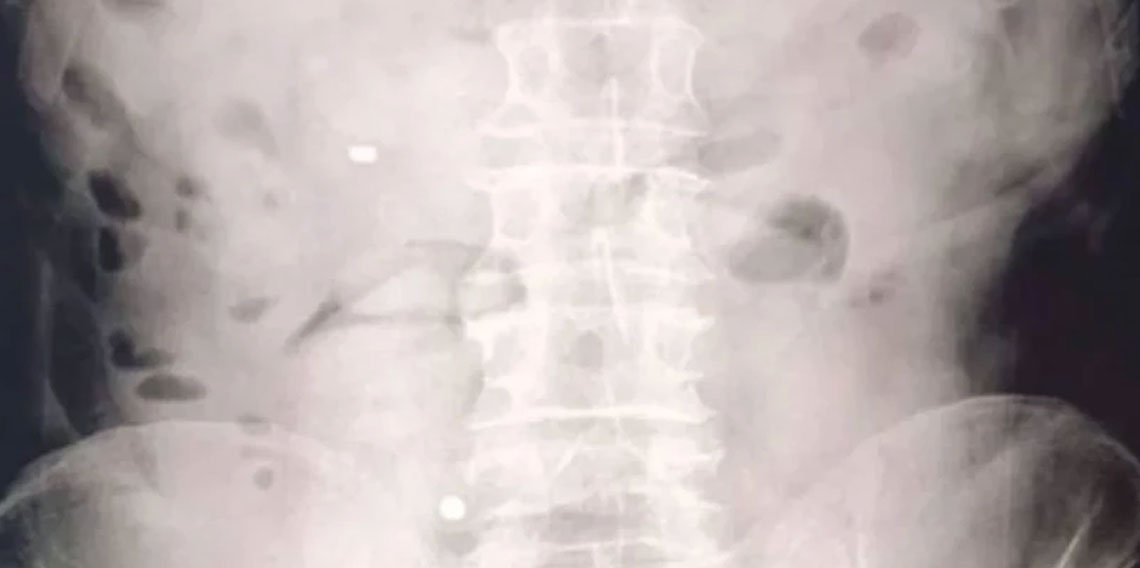

Şüphelilerin hastanede yaptırılan kontrolleri ve çekilen röntgen filmleri sonucunda mide ve bağırsaklarında çok sayıda uyuşturucu madde içeren kapsül bulunduğu tespit edildi.

Hastanede kontrollü şekilde gözetim altında tutulan şüphelilerden tıbbi müdahaleler neticesinde toplam 93 parça halinde 1 kilo 70 gram metamfetamin ele geçirildi.